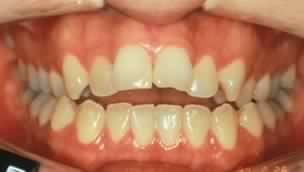

Lo studio della genesi delle malocclusioni ha evidenziato come queste siano dovute al venir meno della capacità di compensazione e di adattamento del sistema occlusale rispetto a discrepanze insorte durante lo sviluppo e la crescita dei piani occlusali posteriori.

Il loro orientamento, se attentamente programmato, è in grado di prevenire in età infantile o risolvere malocclusioni nell’adulto che, diversamente, avrebbero trovato una soluzione solo attraverso la chirurgia.

La malocclusione può pertantoleft essere studiata ed analizzata in termini numerici, correlando l’inclinazione dei piani occlusali alle misure antropometriche del cranio ed alle inclinazioni sia delle eminenze articolari che all’inclinazione delle guide funzionali dei denti (guida canina).